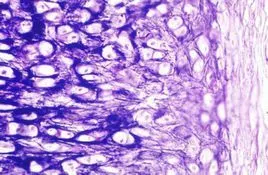

人软骨细胞培养指南

纤维层 软骨细胞

软骨细胞

data-lemmaid="3240196">软骨组织 /a>,由软骨细胞和细胞间质组成